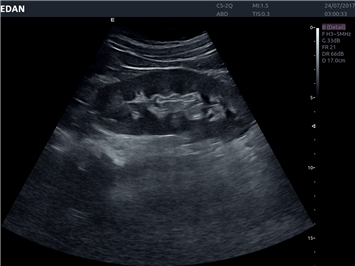

EDAN Acclarix LX4

Расширьте свои представления. Использование усовершенствованной платформой Acclarix система LX4 обеспечивает непревзойденную четкость изображений и интеллектуальный рабочий процесс для всех пользователей, являясь при этом наиболее экономичным решением.

EDAN Acclarix LX4 представляет собой инновационную ультразвуковую систему, построенную на усовершенствованной платформе Acclarix. Сочетание высокого качества визуализации с интеллектуальным рабочим процессом делает эту систему оптимальным выбором для клиник, ценящих эффективность и экономичность.

• Общей визуализации

• Акушерства и гинекологии

• Кардиологических исследований